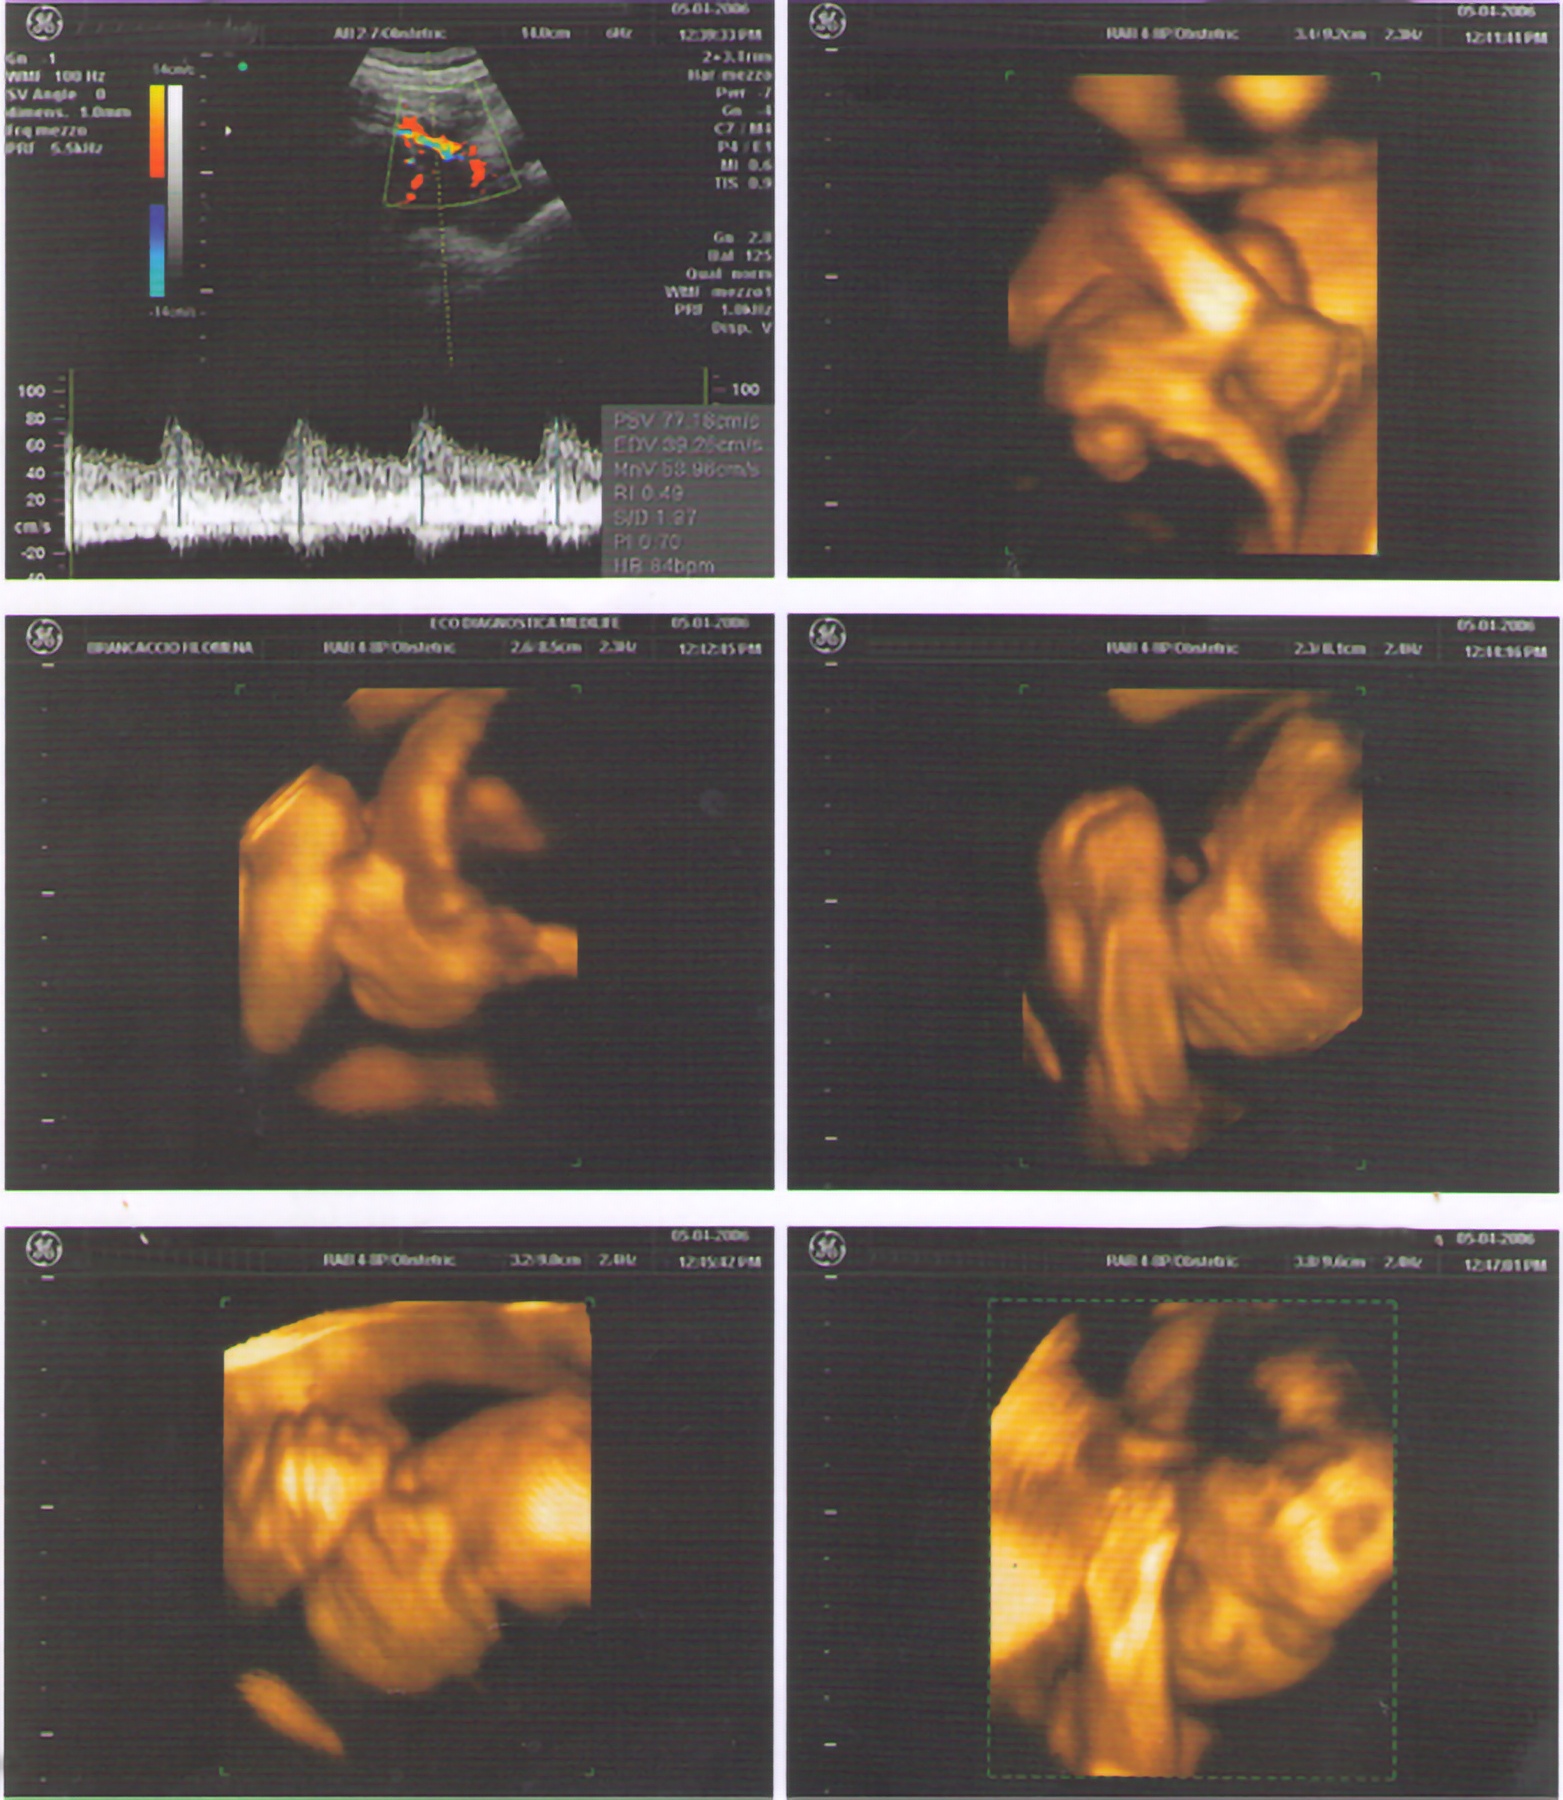

Gallery ECO